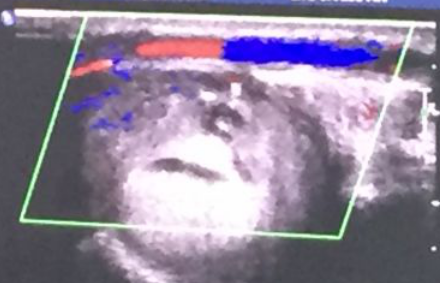

血液透析血管通路的建立与维护:科室拥有血管通路医护团队,设有血管通路专病门诊,多学科协同术前彩色多普勒血管超声检查、术中超声引导以及术后通路超声复查、复杂血管通路及中心静脉的CT血管成像(CTA)和数字减影血管造影(DSA),可开展经皮B超引导下内瘘血管腔内成形术(PTA)、肢体静脉动脉内瘘手术、中心静脉血透导管置入术以及DSA下中心静脉狭窄球囊扩张后建立血透导管等疑难复杂通路的问题。

(2)肢体动脉静脉内瘘(AVF)并发症处理:

(3)B超引导下经皮腔内血管成形术(PTA):

图 超声引导下PTA球囊封堵治疗假性动脉瘤术前后对比